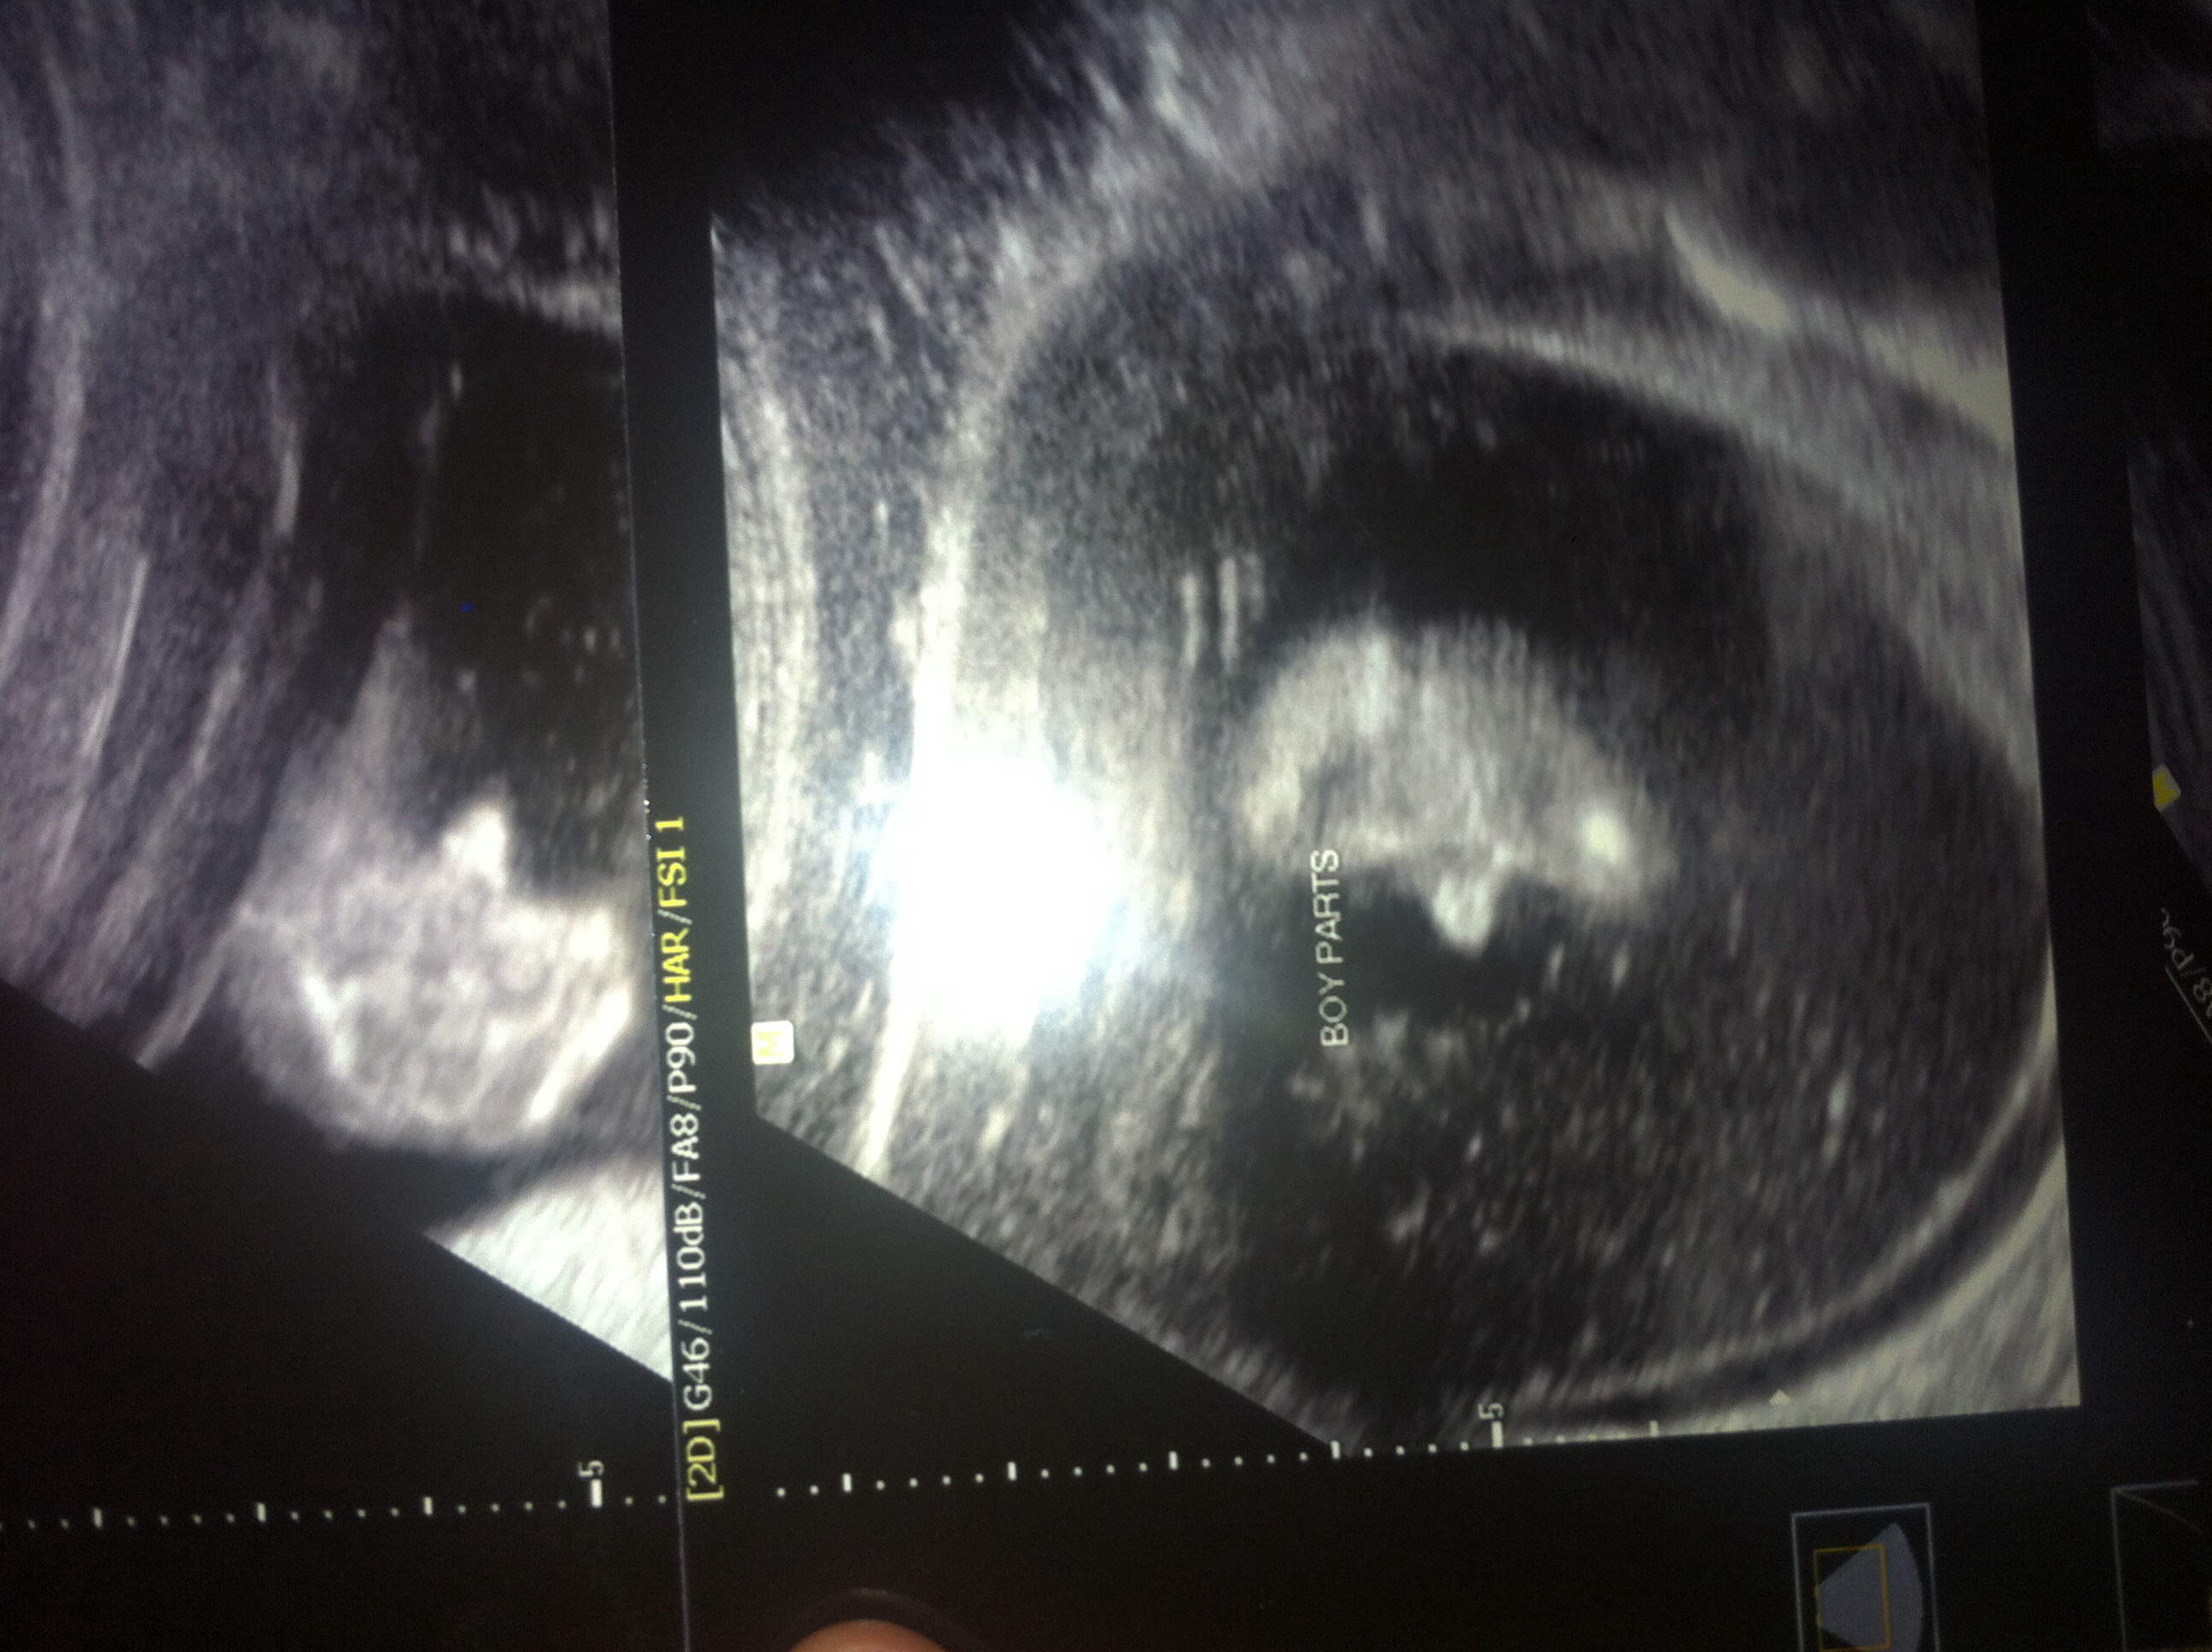

I paid to find out early I was 14w and 6d the tech said boy but I think girl, what do y'all think???

• I don't think it's a good potty shot. My girls had 3 distinct lines.

• I just didn't think boys had 2 penises.. And I read the other parts don't develop until 16 weeks..

On to the kid, my girl had 3 distinct lines & I don't see that in your scan, OP. My guess would be boy for you, that looks like a shot of 2 testicles not dos peens. If you don't want to believe the tech, don't. Looks like you might have to deal with the disappointment of not knowing for sure for Christmas.

• Looks like a boy to me.. A girl would have that hamburger look... Or three lines

• Have you gotten a second opinion yet? I really want to know the outcome.. What about other potty shot pictures.. Do they all look like this? I too went to an early elective that I paid for at 15 weeks 1 day and mine was a boy, but I don't think our pictures look alike.. Who knows that maybe he/she was moving and making the picture look funny .. Anyway keep updated and let us know the outcome! Also here's my pic!